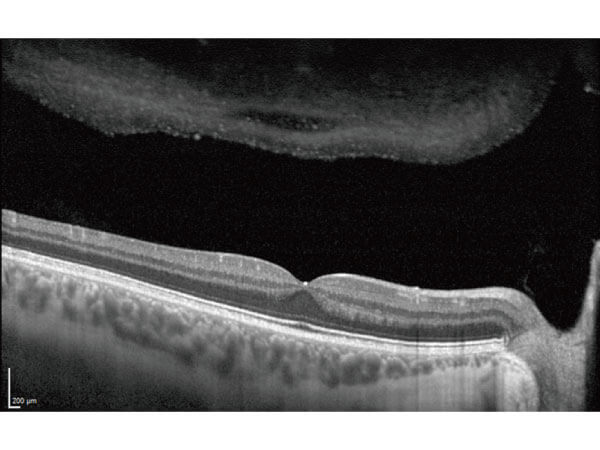

醫療設施:飛秒雷射白內障手術

#完美囊袋切割,水晶體理想置放。 #飛秒雷射細切硬核水晶體,減低超音波能量釋放傷害眼睛結構。 #建議售價: 6萬5